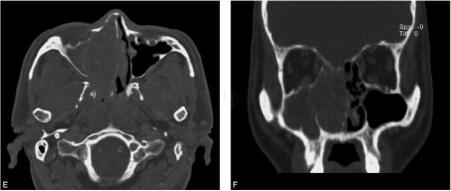

图2 鼻窦MR平扫及增强扫描:图A、图B、图C为横断面T1WI、T2WI及增强扫描,图D、图E为冠状面T2WI及T1WI增强扫描,可见右侧鼻腔内占位病变,形态不规则,内部信号混杂,增强后可见不均匀中度强化。右上颌窦及蝶窦可见黏膜增厚,呈长T1、长T2信号影,增强后可见线状环形强化

鼻腔内占位病变,形态规则或不规则,因肿瘤成分复杂信号变化较大,增强后可见轻度不均匀强化。MRI对周围组织显示较好,可以显示肿瘤导致的继发改变。例如,肿瘤阻塞鼻窦开口引起鼻窦炎症,MR可以清楚显示增厚鼻窦黏膜,使之与肿瘤自身相区分。